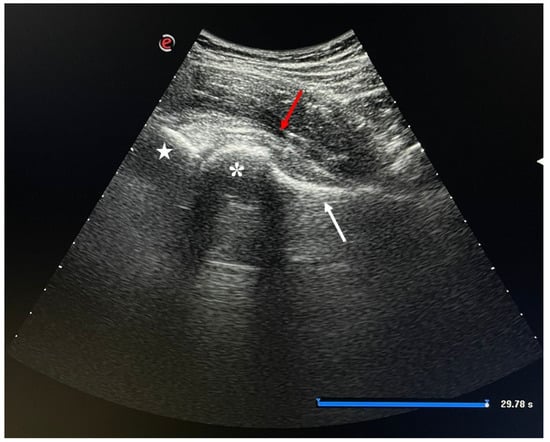

4.1.2. Injection Procedure